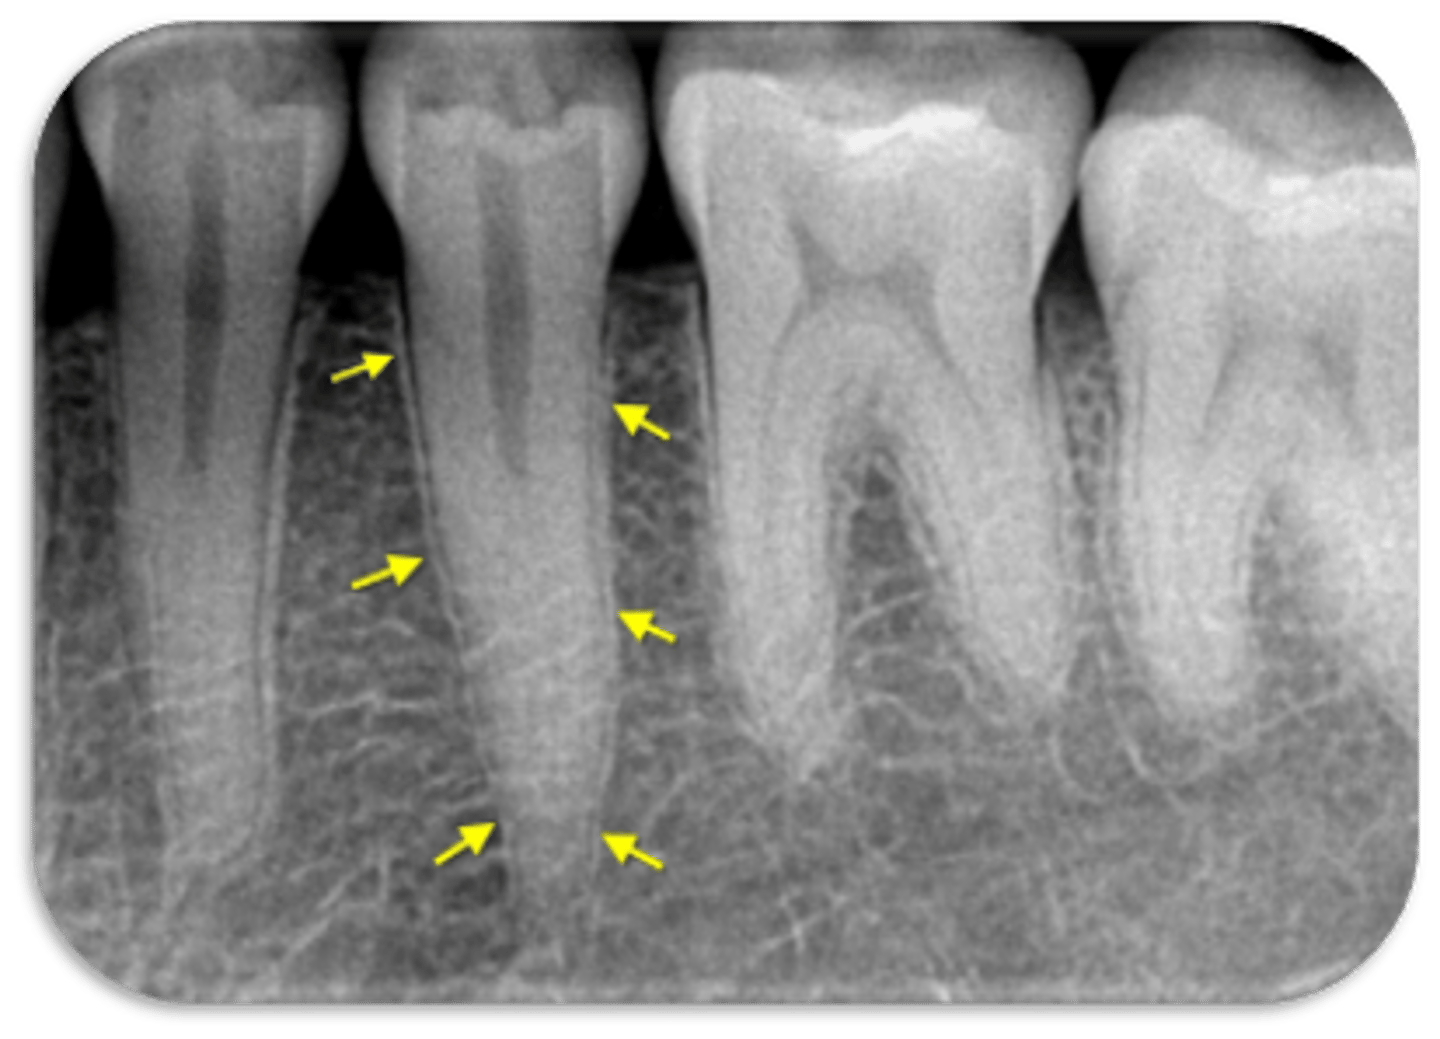

vertical root fracture

ID the problem:

- May not show on PA radiographs

Presents with signs of:

- J-shaped lesion/lateral radiolucency

- Isolated deep pocket

- Coronally located swelling or sinus tract